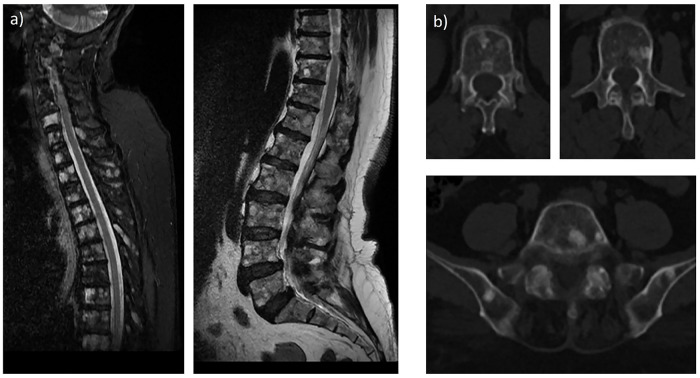

通过影像学识别骨转移是必要的,对小叶乳腺癌患者可能具有挑战性。我们报告了一位66岁的小叶性乳腺癌患者,她接受了18F-氟脱氧葡萄糖正电子发射断层扫描/计算机断层扫描(FDG PET/CT)进行分期。18F-FDG PET/CT显示原发肿瘤细胞中FDG摄取极少。脊柱和骨盆骨可见明显的硬化性病变,FDG密度低。随后的Tc-99m二膦酸亚甲基骨扫描结果并不显著。磁共振多重成像(MRI)显示骨转移。MRI对浸润性小叶癌可能是有益的。当18F-FDG PET/CT评估可能困难且受限时,MRI有助于改善转移性评估,特别是在仅骨和骨为主的转移性恶性肿瘤中。

Identifying osseous metastases by imaging is essential and may be challenging in patients with lobular breast cancer. We present a case of a 66-year-old woman with lobular breast cancer who underwent 18F- fluorodeoxyglucose positron emission tomography/computed tomography (FDG PET/CT) for staging purposes. 18F-FDG PET/CT reveals minimal FDG uptake in the primary tumor cells. Prominent sclerotic lesions with low FDG avidity are seen in the spinal and pelvic bones. The subsequent Tc-99m methylene diphosphonate bone scan is unremarkable. The magnetic resonance imaging (MRI) reveals bone metastases. MRI may be beneficial in invasive lobular carcinoma. MRI facilitates improved metastatic evaluation, especially in bone-only and bone-predominant metastatic malignancies, when assessment with 18F-FDG PET/CT may be difficult and constrained.